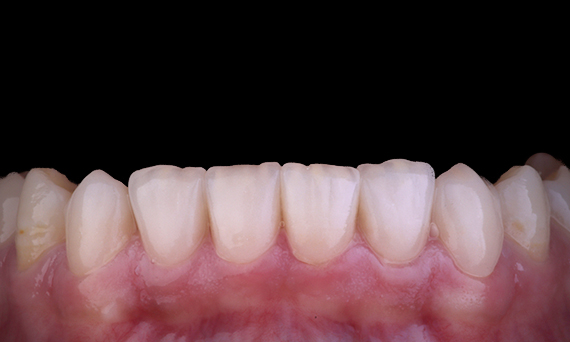

Il est assez courant d’observer les fissures et les fractures associées aux restaurations d’amalgame, d’autant plus qu’elles augmentent en taille, car il s’agit de restaurations « non collées ». Bon nombre de ces dents sont structurellement compromises et une approche adhésive et biomimétique est la méthode idéale pour restaurer ces dents. Dans le cadre d’un plan de traitement plus complet, ce quadrant devait avoir deux onlays en céramique indirecte. Les première et deuxième molaires ont été restaurées en une seule visite à l’aide de CEREC Tessera, un disilicate de lithium avancé.

Dr Yo-Han Choi, Sydney, Australie